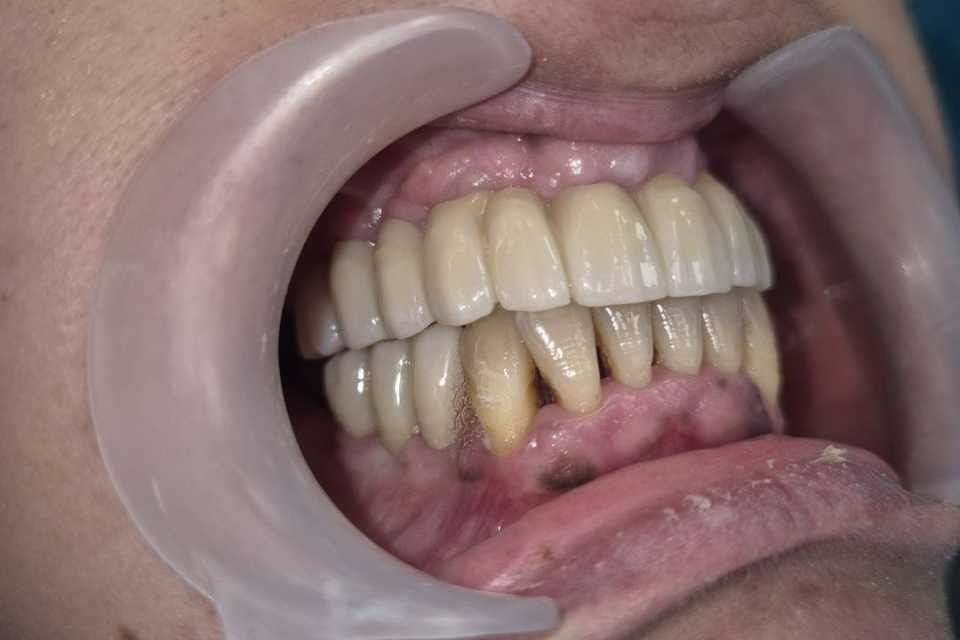

Împreună cu pacienta, am optat pentru un tratament complex, realizat într-o singură ședință. S-au efectuat extracțiile dinților parodontotici, chiuretajul pungilor parodontale și inserarea a 4 implanturi Mega-Gen AnyRidge la nivelul maxilarului. Cu ajutorul capelor multiunit, s-a reușit protezarea imediată, prin aplicarea unei lucrări provizorii din acrilat, la doar 24 de ore de la intervenție. După 2 luni, tratamentul a fost finalizat prin realizarea unei lucrări definitive, înșurubabile, din ceramică pe suport de zirconiu, cu 12 elemente.

La nivelul mandibulei, reabilitarea zonelor laterale premolar-molar s-a realizat prin inserarea a câte două implanturi pe fiecare parte, protezate după 2 luni cu două lucrări din ceramică pe suport de zirconiu, cimentate. Dintii restanți ai mandibulei au fost conservați după tratamentul parodontal și solidarizați printr-o contenție linguală.